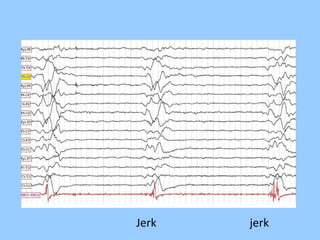

1. The document discusses EEG patterns and findings in various neurological conditions seen in children. It includes descriptions of normal EEG findings as well as abnormal patterns seen in conditions like absence seizures, West syndrome, benign childhood epilepsy with centrotemporal spikes, Lennox-Gastaut syndrome, non-convulsive status epilepticus, subacute sclerosing panencephalitis, and herpes encephalitis.

2. Case studies are presented with clinical histories and EEG findings to illustrate different pathologies. Treatment options are also mentioned for many of the conditions.